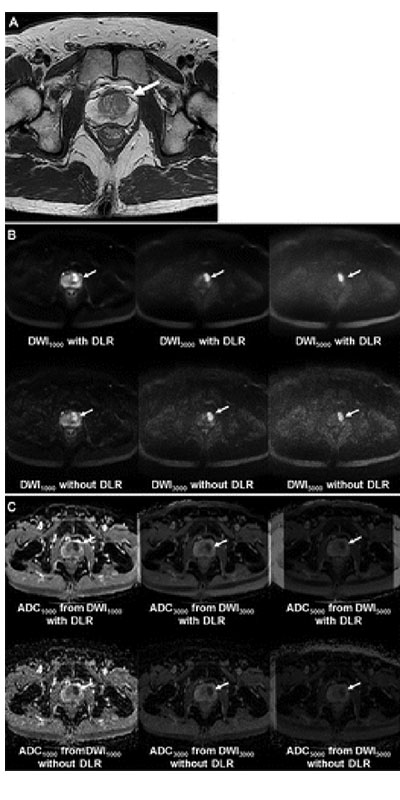

Images in a 51-year-old man with left transition zone prostate cancer. (A) T2-weighted MRI scan shows hypointense 2.1-cm prostate cancer (arrow) in the left transition zone. (B) MRI scans from diffusion-weighted imaging (DWI) with a b value of 1000 sec/mm2 (DWI1000), DWI with a b value of 3000 sec/mm2 (DWI3000), and DWI with a b value of 5000 sec/mm2 (DWI5000) with or without deep learning reconstruction (DLR). The cancer shows high signal intensity (arrows). (C) Apparent diffusion coefficient (ADC) maps obtained from DWI1000, DWI3000, and DWI5000 (ADC1000, ADC3000, and ADC5000, respectively) with or without DLR. The cancer shows low signal intensity on all ADC maps (arrows).

Ueda et al, Radiology 2022; 000:1–9 ©RSNA 2022